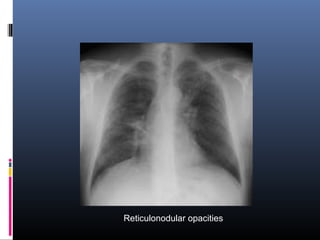

 Reticular, reticulonodular, or focal alveolar

opacities are most characteristic

Reticular opacities

Reticulonodular opacities

Focal alveolar opacities

Conventional chest radiographs  Over 90% of patients with sarcoidosis manifest abnormalities on chest radiographs  Commonest feature-BHL (50-80%)  Concomitant enlargement of right paratracheal lymph nodes is common  Pulmonary parenchymal infiltrates (25 to 50%)

 Parenchymal infiltratesare often symmetrical and bilateral, with a predilection for the central (rather than peripheral) regions and upper lobes (particularly posterior and apical segments)  Reticular, reticulonodular, or focal alveolar opacities are most characteristic